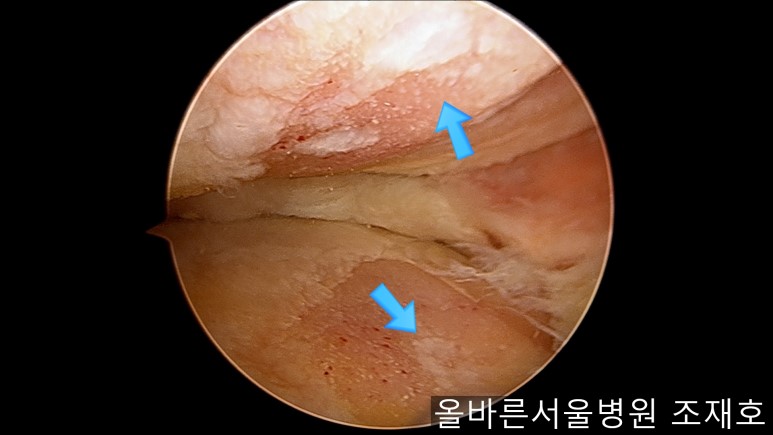

与内侧对照,外侧的软骨及软骨板无损伤。

在股骨部位用CARTISTEM注射用4mm激光钻细密打孔,并确保软骨板不倒塌。不用切开通过关节镜即可完成手术。

如图,尽量细密打孔。